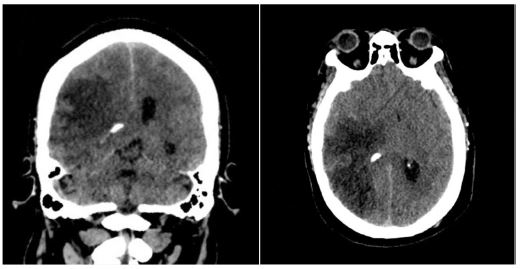

Twenty-four hours post-admission, his neurological status worsened (GCS decreased by 4 points), and a CT scan showed a significant midline shift. A right-sided frontotemporoparietal decompressive craniectomy was performed. Postoperatively, his GCS improved to 14 and motor strength improved to 3/5 on the Lovett scale (Figure 2). A Computed Tomography Angiography (CTA) performed 48 hours after surgery showed restored flow in the M1 and distal branches of the right MCA (Figure 3). A confirmatory cerebral angiogram at two weeks demonstrated patent flow throughout the MCA distribution (Figure 4).

Figure 4: Cerebral angiography 2 weeks later, showing recanalization of the right MCA.